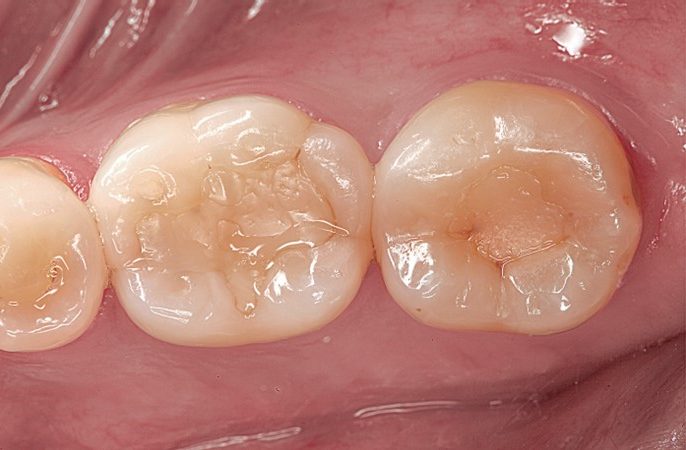

Hình 1. Hình ảnh mặt nhai trước điều trị của các phục hồi composite bị khiếm khuyết trên R46, 47 và có sâu răng tái phát.

Hình 10. Hình ảnh mặt nhai sau điều trị cho thấy sự tích hợp hài hòa giữa hình dạng giải phẫu và độ sâu bên trong của màu sắc.

Hình 11. Tái khám sau 2 năm và 5 năm. Lưu ý độ mòn nhẹ ở bờ viền R47.